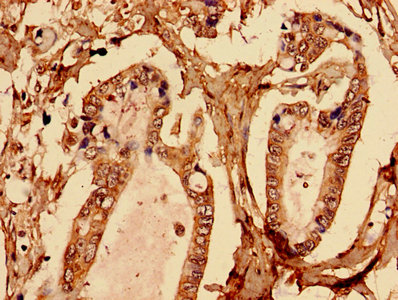

Immunohistochemistry analysis of human placenta tissue using CSB-PA002683EA01HU at dilution of 1:100